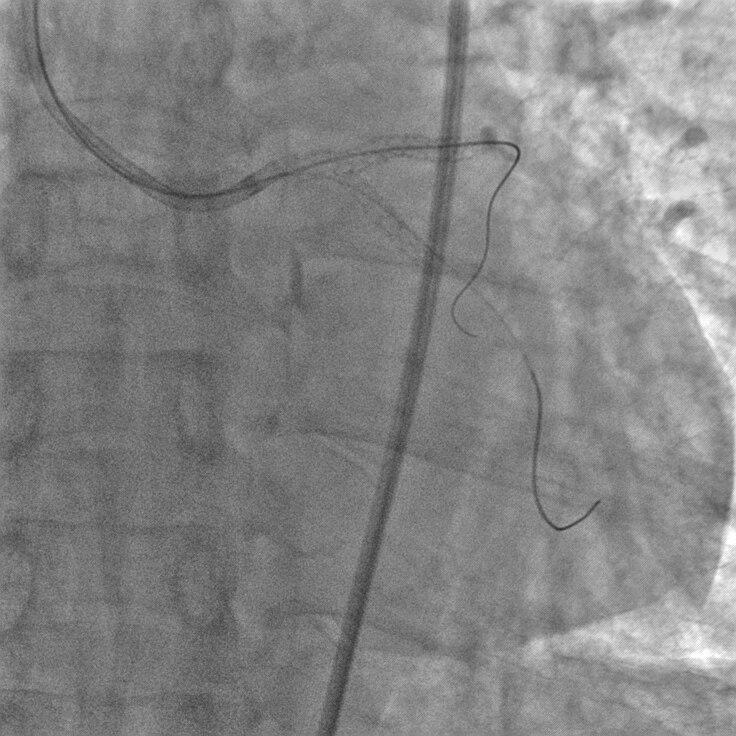

Великолепное качество изображения при низкой дозе

Цифровой квадратный плоскопанельный детектор Revolution имеет уникальную конструкцию, представленную фотодиодной матрицей с аморфным кремнием на монолитной основе без характерных швов. Толщина сцинтиллятора и электронный шум оптимизированы таким образом, чтобы максимально увеличить эффективность использования дозы облучения.

Детектор обладает одним из самых высоких в отрасли коэффициентом квантовой эффективности (DQE). Высокий DQE позволяет получать изображения более высокого качества при применении тех же параметров дозы или изображения прежнего качества при сниженной дозе облучения. Функция Smart Fluoro оптимизирует качество изображения на всех уровнях дозы облучения, обеспечивая возможность использования минимальной дозы облучения при оптимальном качестве изображения.